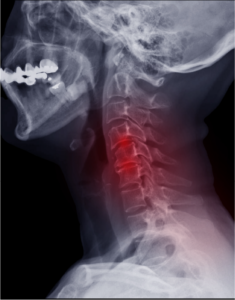

Cervical Fracture

The neck is made up of seven tiny bones called cervical vertebrae (C1-C7). These are protected by spongy vertebral disks present between them and supported…

Whiplash

Cervical spine refers to neck portion of spine, and cervical spine conditions may result from overuse injuries, trauma and certain diseases.